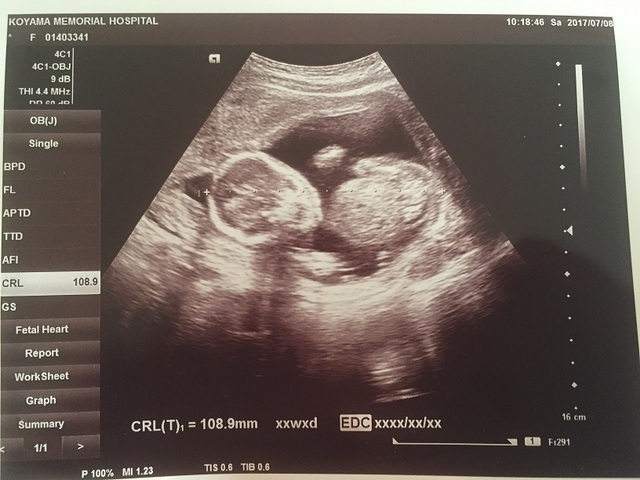

17週6日(17w6d・男の子)|よぴ1126 さん(28歳)

エコー写真撮影時のエピソード:

初めて4Dエコーをした時で、2Dの時とは違って、赤ちゃんの姿がはっきり見えることに感動したのを覚えています。お顔や姿がとてもかわいかったです。その思い出のエコー写真と一緒に妊娠期の思い出を残したくて、妊娠29週の時にマタニティフォトを撮りました。